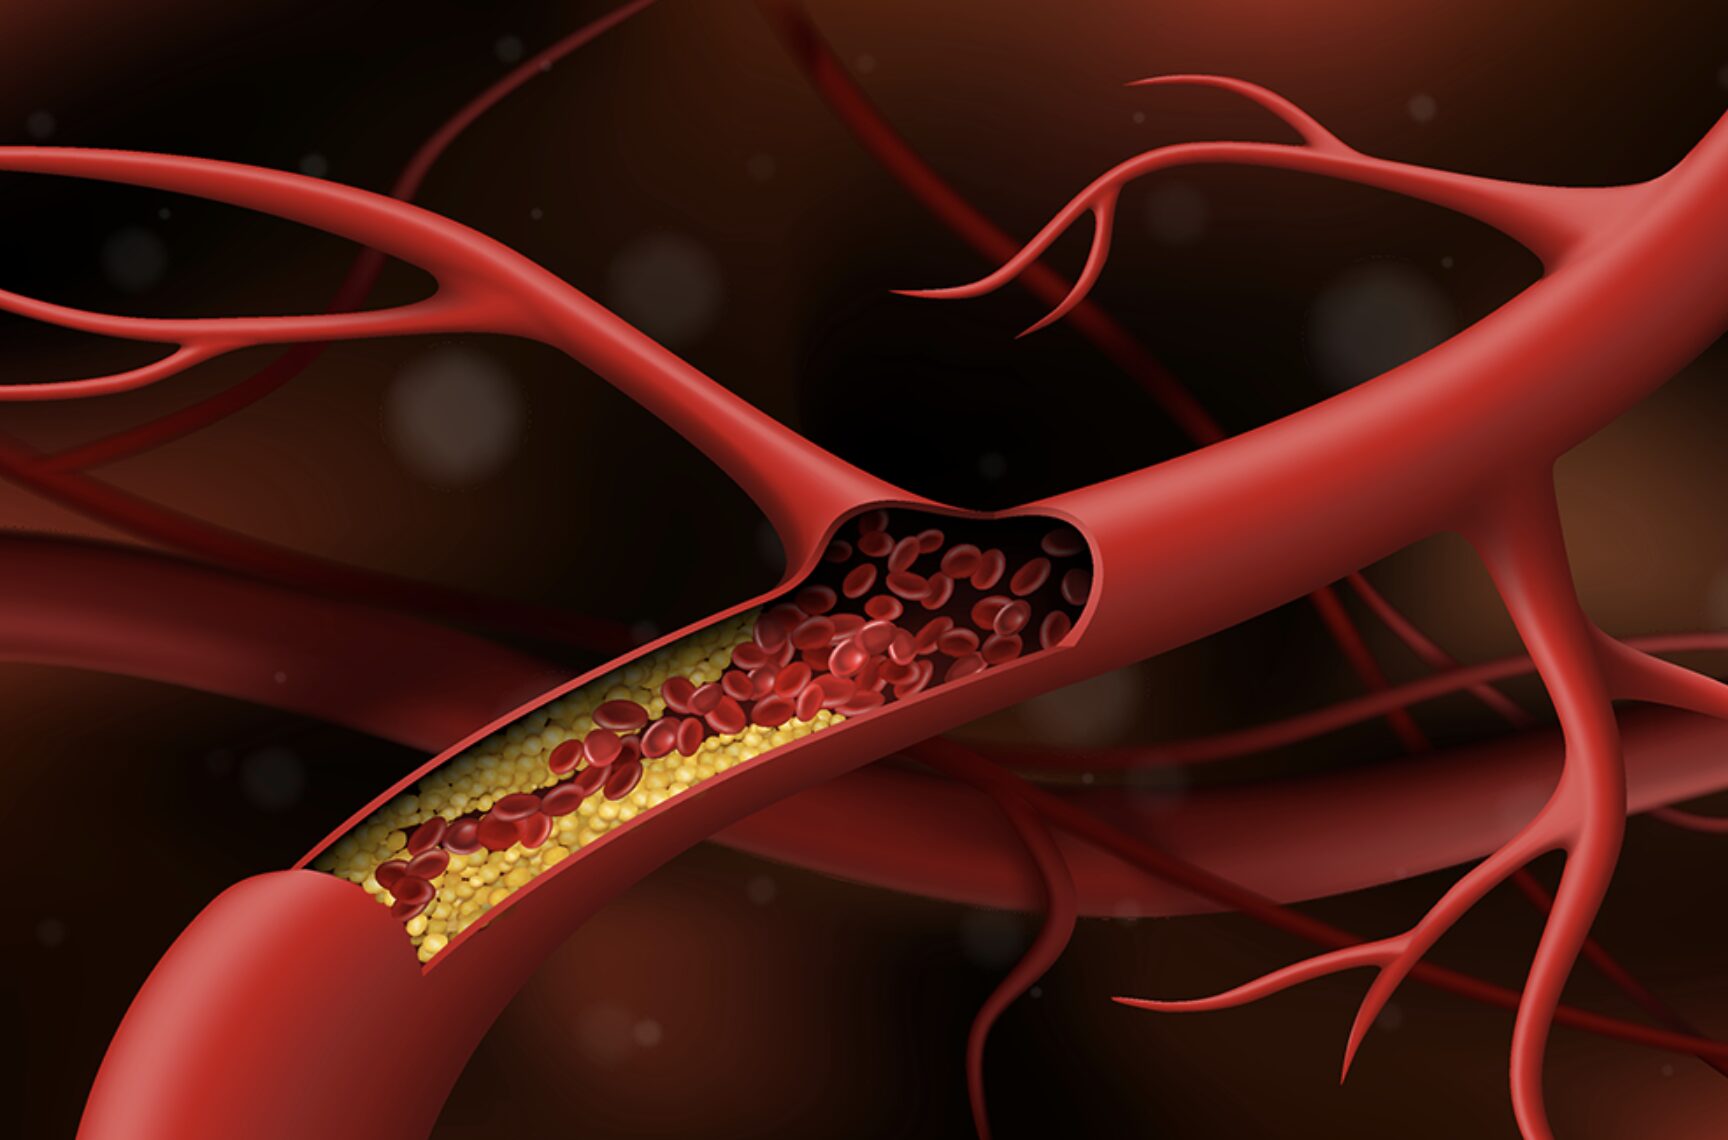

Đột quỵ do tắc động mạch thân nền

Đột quỵ do tắc hoàn toàn động mạch thân nền gây ra một số triệu chứng như: đột ngột té ngã, yếu liệt tứ chi, hôn mê, ngưng tim ngưng thở. Đặc biệt, tỷ lệ tử vong có thể lên đến 90% nếu bệnh nhân không được cấp cứu ngưng tim ngưng thở kịp thời.